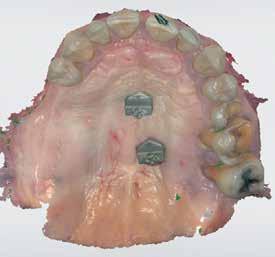

72 FDC 2026 Speaker: Full Arch Implant Reconstruction in the Digital Era: Past, Present and Future